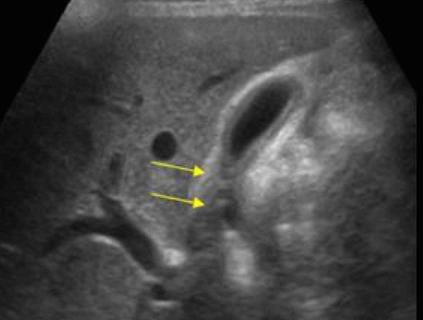

- 1cm 미만의 고에코의 종괴 (hyperechoic mass) : 담석에 비해 에코가 낮고, 담낭벽보다는 고에코로 보임

- 담낭벽에 붙어 체위변화 시 이동이 없다

- 후방음영이 없다